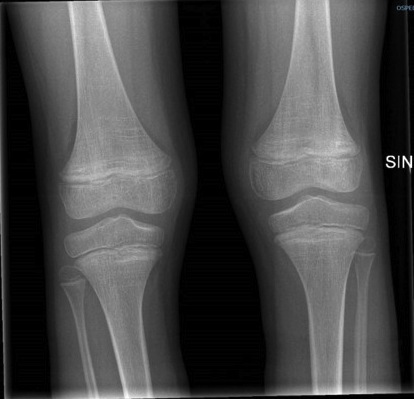

Paziente 2 - Maschio di 6 anni con disturbo dello spettro autistico e alimentazione selettiva. Comparsa di zoppia con rifiuto della deambulazione e petecchie agli arti inferiori. Viene sospettata una porpora di Schönlein-Henoch. Per il persistere della sintomatologia articolare esegue Rx arti inferiori che mostra alterazioni suggestive di un quadro carenziale (Figura 1). Il dosaggio della vitamina C conferma il sospetto di scorbuto.